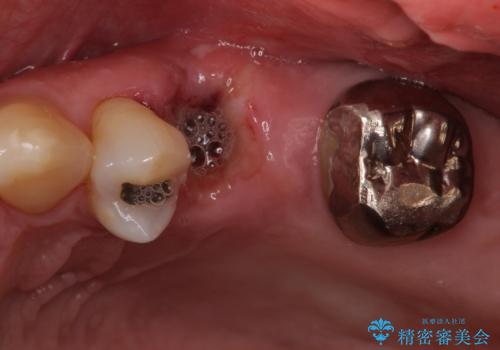

部分矯正を併用した奥歯のインプラント補綴治療

ブリッジの支台を抜歯したことで2本のインプラントが必要であり、その後方はインプラント埋入に必要な骨量が不足していたため、上顎洞粘膜の挙上を行うこととしました。

また、残っている最後方歯は手前に倒れてきていたため、部分矯正により奥に移動させてから、インプラント埋入を行うこととしました。